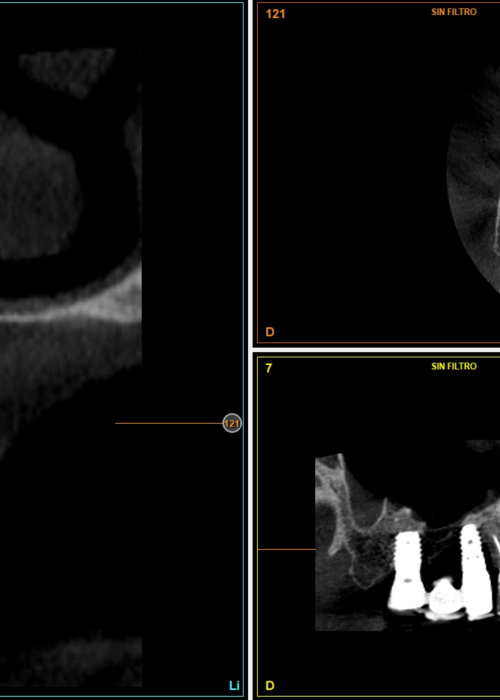

Atrofia extrema vertical y horizontal combinada en sectores posteriores mandibulares. Uso de implantes cortos y expansión de cresta en dos fases con implantes transicionales

Extreme vertical and horizontal atrophy combined in posterior mandibular sectors; use of short implants and 2-phase ridge expansion with transitional implants: A clinical case

Atrofia combinada maxilomandibular. uso de implantes cortos y estrechos (BTI® CORE y BTI® 3.0)

Injerto en bloque en combinación con la técnica de split en dos fases para la rehabilitación de un caso de gran reabsorción ósea del maxilar en anchura

Block grafting in combination with the two-stage split technique for the rehabilitation of a case of severe bone resorption of the maxilla in width